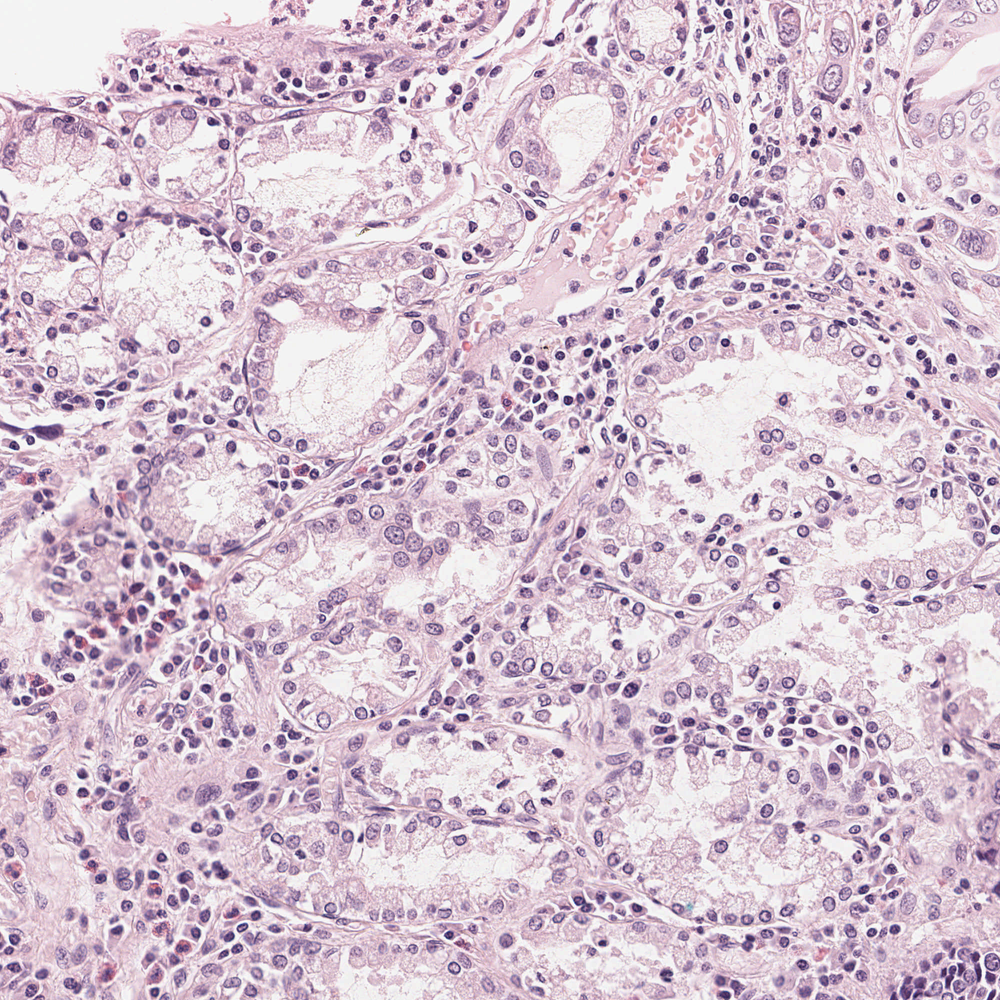

Immagine di tessuto di stomaco con colorazione ematossilina ed eosina, originale (sinistra) e normalizzata con STAINS (destra).